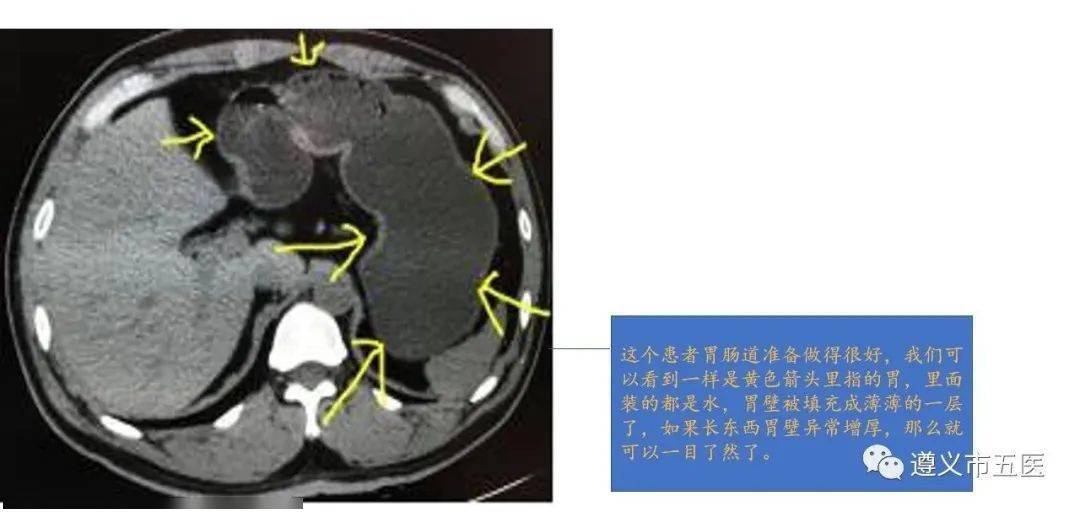

科普||腹部ct检查为什么要多喝水?

图片尺寸1080x512